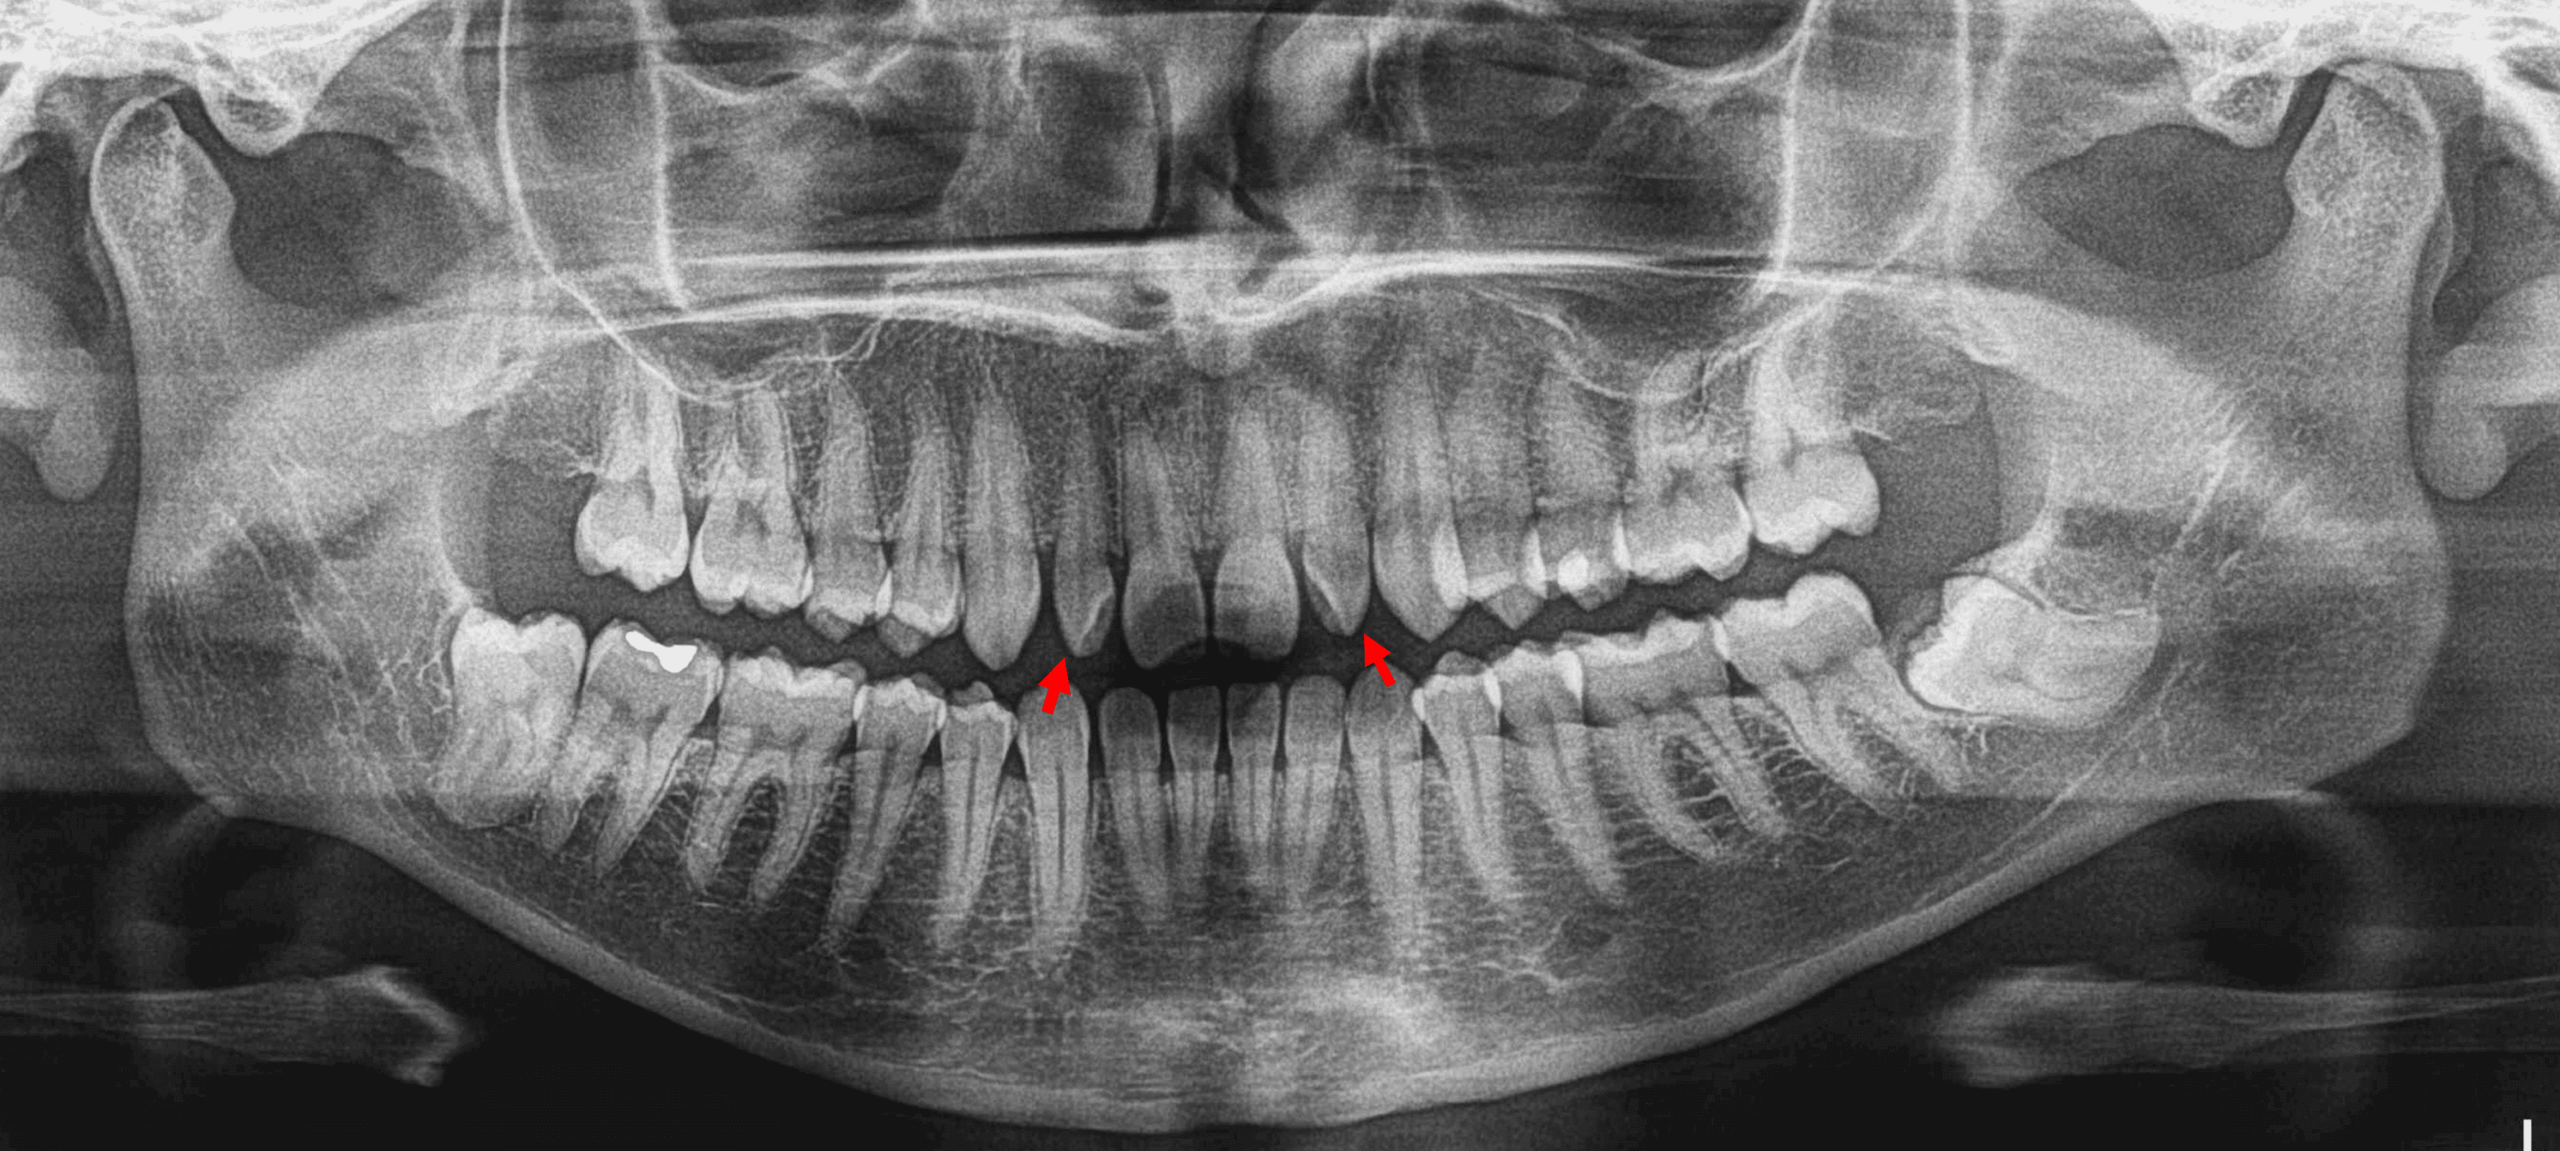

Fig.1

En la evaluación de la radiografía panorámica (Fig.1) se observa la ausencia de los terceros molares superiores y la impactación de los terceros molares inferiores. El órgano dentario 38 se observa en posición mesioangular y las raíces proyectadas sobre la cortical superior del conducto dentario inferior y el órgano dentario 48 se observa impactado contra el borde anterior de la rama ascendente mandibular, con la corona parcialmente erupcionada, con los ápices proyectados sobre el conducto dentario inferior. En el sector anterosuperior se observa una leve disminución del tamaño coronario, así como una alteración en su forma.